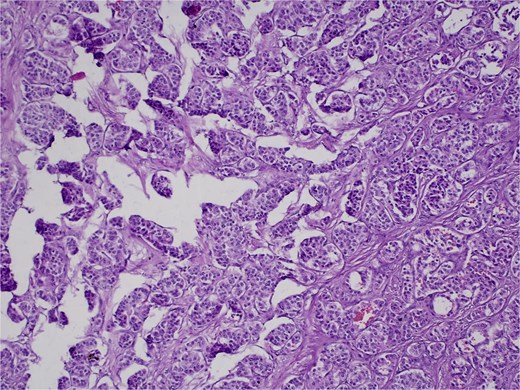

On 27 January 2025, the patient underwent a Whipple procedure (pancreaticoduodenectomy). The surgery included cephalic pancreatectomy with reconstruction through hepaticojejunostomy and gastrojejunostomy in a Roux-en-Y configuration. Gross pathology revealed a firm, white-yellow, indurated mass in the pancreatic head measuring 3.7 × 3.5 × 3 cm with irregular borders and central hardness (Fig. 4). Histopathological analysis confirmed a Grade 1 neuroendocrine tumor (insulinoma), with a Ki-67 index of 2%. The tumor showed direct extension to adjacent pancreatic tissue, the duodenal muscularis propria, the adventitia, and the muscularis of the common bile duct. Five peripancreatic lymph nodes were dissected, three of which were positive for metastases (Figs 5–9).

H&E stain, 100× magnification. Diffuse infiltration of pancreatic parenchyma by tumor cells with desmoplastic stroma.